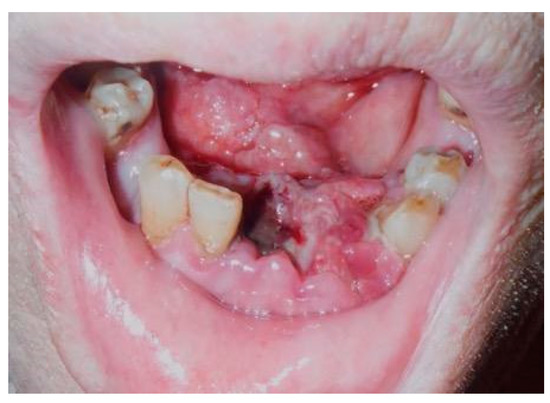

A 68-year-old Japanese man referred to the Department of Oral and Maxillofacial Surgery at the University Hospital of Tsukuba, complaining of a mass in the lower gingiva, one month after extraction of his frontal teeth. His medical history revealed diabetes mellitus, hypertension, hydrocephalus, and cerebral bleeding. He had no history of animal breeding. His general condition was good, and his face was symmetrical without trismus. The regional lymph nodes were not swollen. Intra-oral examination showed an irregular surface and an elastic hard mass with a necrotic ulcer between the right second premolar and the left first premolar, extending to the right floor of the mouth and measuring approximately 29 × 26 mm (Figure 1).

Figure 1.

Necrotic ulcer. Intra-oral examination shows an irregular surface and elastic hard mass with a necrotic ulcer, which measures approximately 29 × 26 mm.